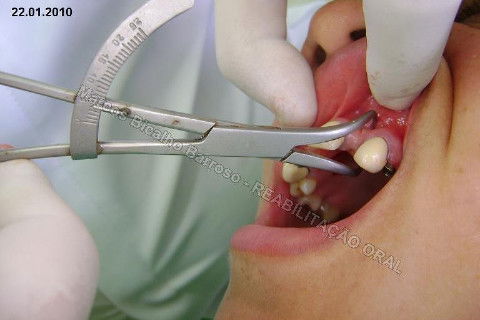

Paciente sexo feminino, 40 anos, queixava-se da situação da PPR superior, sem estabilidade, fraturas constantes nos dentes instalados. Sua vontade era resolver somente o problema da arcada superior, por questões financeiras. Logo no exame clínico inicial verifiquei a necessidade da reabiltiação inferior, pois este caso consistia em desarmonia oclusal severa, principalmente pela extrusão dos elementos 13,14 e 15 devido ausência de várias unidades inferiores. A proposta aceita pela paciente foi a instalação de 5 implantes na mandíbula + 5 implantes na maxila + tratamento endodôntico, osteoplastia e gengivoplastia nos dentes extruídos, incluindo núcleos metálicos e coroas em metalocerâmica (13,14,15). As coroas sobre implantes serão incialmente provisórias em resina fotopolimerizável e posteriormente metalocerâmica, de acordo com as possibilidades da paciente. Os procedimentos nos elementos extruídos serão apresentados em momento oportuno.

Fotos do caso